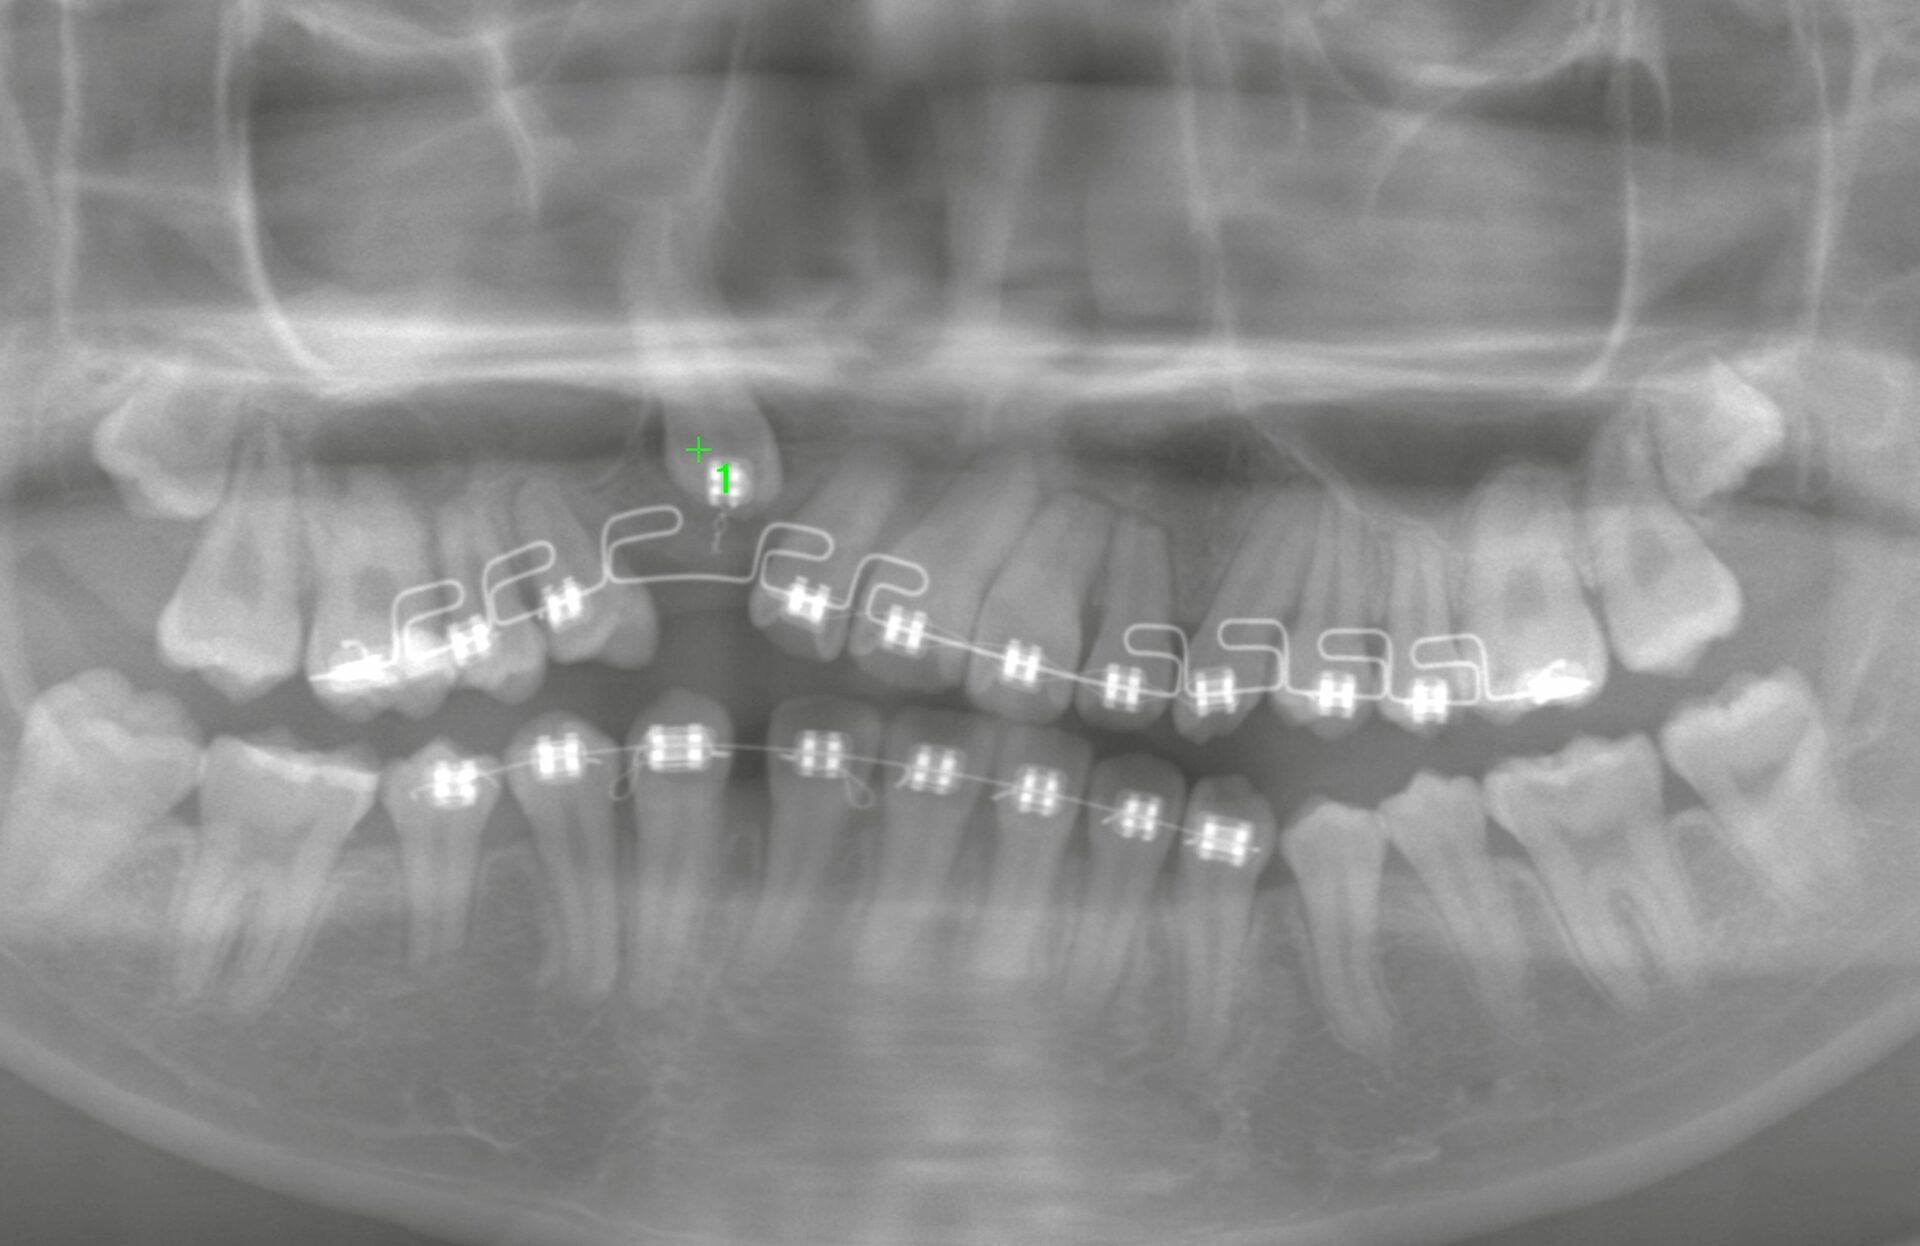

本日は、矯正歯科からのご紹介で行った犬歯の外科的挺出処置のケースをご紹介します。

今回の患者様は、矯正治療中の10代の方。

右上の犬歯(糸切り歯)を矯正用のワイヤーで長期間引っ張っていたものの、なかなか萌出せず、「矯正単独では限界がある」と判断され、当院にて外科的アプローチを実施することになりました。

埋伏した歯(主に犬歯や小臼歯など)が矯正治療のみでは動かない場合、歯肉や骨を一部開き、歯に物理的にアクセスして引き出すスペースと動きやすさを与える外科処置のことを言います。

このケースでも、歯肉をフラップ(剥離)し、一部の骨を削合したうえで、歯の脱臼操作を加えました。

今回も、処置後すぐに犬歯に弾力性が出て、牽引しやすくなる状態が得られました。